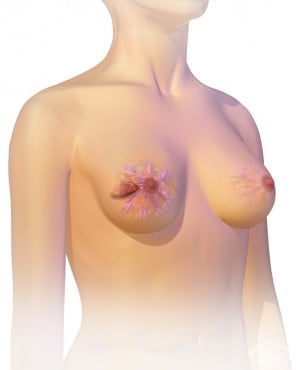

Третият класически симптом на рака на млечната жлеза е срастването на тумора с кожата, при което тя придобива вид на портокалова кора - установява се раздразнена кожа и грапавост.

8.4. Хлътване или болка на зърното

Ракът на гърдата може да доведе до промени във външния вид на зърното.

Хлътването на зърното е друг типичен симптом. То се получава, ако туморният процес е близо до зърното, и при нарастване на рака на гърдата, то се придръпва навътре.

При засягане на зърното от туморния процес се появява и болка.

8.5. Разязвяване или зачервяване на зърното или кожата на гърдата

Разязвяването и зачервяването на зърното или по кожата на ареолата представлява особена форма на рака на гърдата – болест на Paget. Тя се характеризира с екземоподобен обрив по кожата с леко залющване на кожата на зърното. Установява се също и парене, сърбеж и болка в засегнатата област.